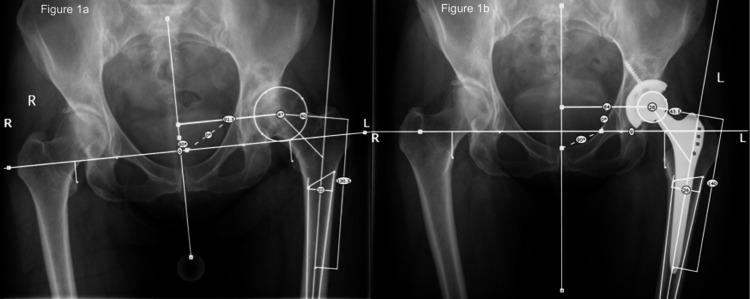

Introduction Leg length and offset are important considerations in total hip arthroplasty (THA). Navigation systems are capable of providing intra-operative measurements of leg length and offset, and high accuracy has been shown in experimental studies. This study assesses the accuracy of an imageless navigation system with a pinless femoral array (Hip 5.1, BrainLAB, Feldkirchen, Germany) in measuring leg length and offset changes in vivo. Methods A prospective, consecutive series of 37 patients undergoing navigated THA were included in the study. Intra-operative measurements of leg length and offset were recorded using the navigation system. For each patient, pre- and post-operative digital radiographs were scaled and analyzed to provide radiographic measurements for comparison. Results Measurements of leg length change made by the navigation system showed a strong correlation with the size of change measured radiographically (R = 0.71; p<0.0001). The mean difference between the radiographic and navigational measurement was 2.6mm ± 3.0mm (0.0-16.0mm) (mean, SD, range). The navigation system was accurate to within 1mm of the radiographic measurement in 49% of cases, within 2mm in 66% of cases, and within 5mm in 89% of cases. Measurements of offset change by the navigation system also showed a correlation with radiographic measurements, albeit less pronounced (R = 0.35; p=0.035). The mean difference between navigational and radiographic measurements was 5.5mm ± 4.7mm (0.0-16.0mm) (mean, SD, range). The navigation system was accurate within 1mm of the radiographic measurement in 22% of cases, within 2mm in 35% of cases, and within 5mm in 57% of cases. Conclusions This research demonstrates in vivo that an imageless, non-invasive navigation system is a reliable tool for intra-operative leg length (accurate within 2mm) and to a lesser extent offset measurement (accurate within 5mm) when compared to standard practice of plain film radiographs.

本研究纳入了37例接受导航THA的连续前瞻性患者系列。使用导航系统记录术中下肢长度和偏心距的测量值。对每位患者的术前和术后数字X线片进行缩放和分析,以提供用于比较的影像学测量值。